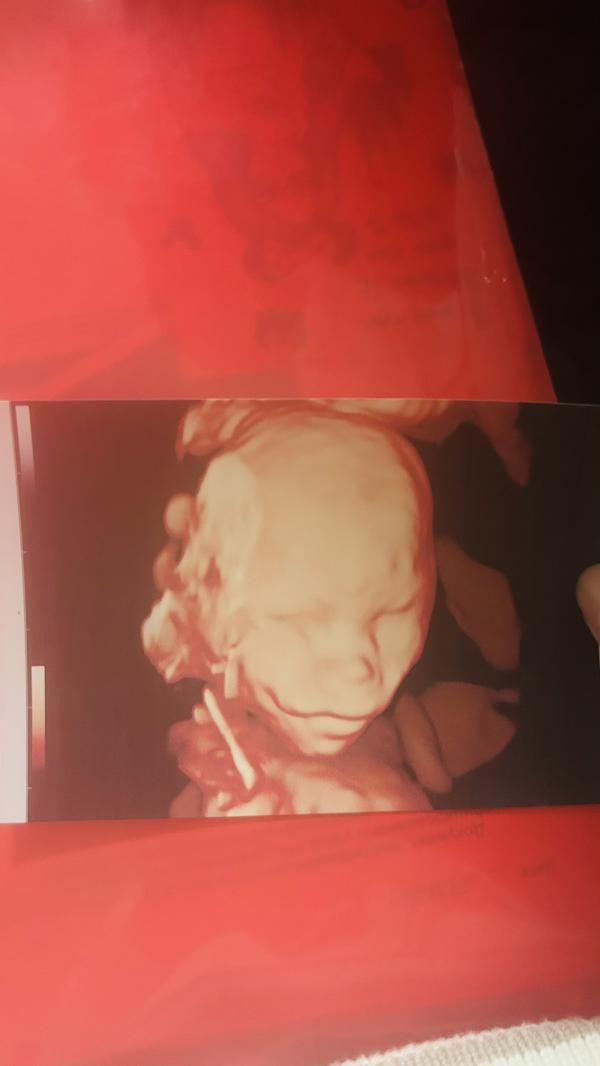

Ну вот мое узи в 16 недель))

Нормально 😂👌

Лицо ребёнка такое ‘хмм’ 🤔🙂